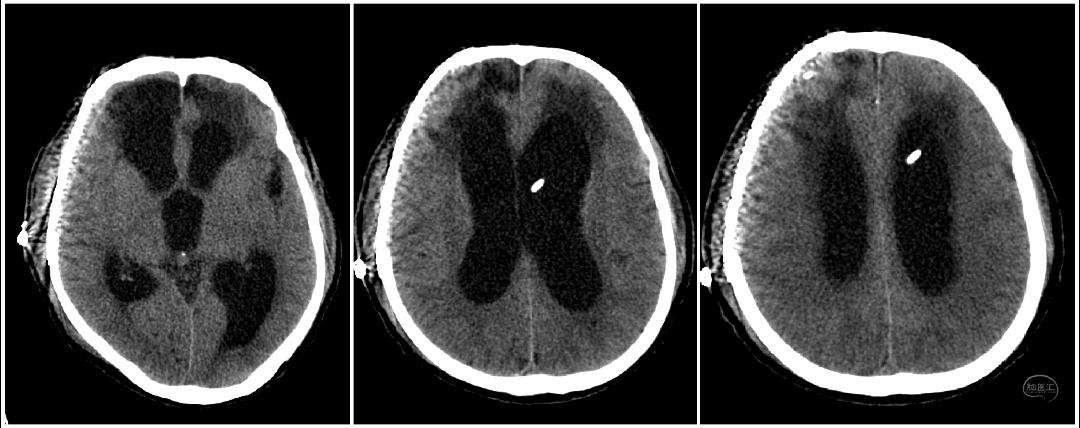

近期陕西省核工业二一五医院神外监护室完成西北首例低颅压性脑积水ProSA+ProGAV系统分流手术。患者老年男性,半年前因重型颅脑损伤在本院行开颅手术治疗,术后意识清楚,好转出院。本次因智力减退步态迟缓10天入院。入院头颅CT及核磁提示(脑室系统扩大,周围可见间质水肿;中脑导水管通畅)。

患者临床症状表现为痴呆、步态不稳、记忆力减退、大小便失禁症状。既往有颅内感染病史,腰穿测压力为70mmH2O,脑脊液蛋白含量高。在颅骨修补手术后,患者意识障碍较前加重。术后头颅CT(脑室系统较前扩大)。采取侧脑室额角穿刺安置Ommaya囊,通过侧脑室穿刺管内水柱高度判断侧脑室内压力,测患者脑室内压力为60mmH2O。诊断为低颅压性脑积水。

针对低颅压脑积水最常用的治疗方法为脑室-腹腔分流术。进行治疗过程中分流管的选择对于患者的预后质量具有重要影响,分流不足与分流过度均会造成严重并发症,不仅影响治疗效果,甚至会导致患者死亡。谢国强主任组织科室研究讨论制定治疗方案。患者脑脊液指标正常后,计划行脑室腹腔分流术。本次选用ProSA+ProGAV系统可调压式分流管为是西北地区首例。proSA是首个允许在直立位,以及在直立位与仰卧位见的任何角度进行开启压力调节的脑积水阀门,其开启压力随患者体位变化而改变。当处于水平体位时,重力装置无阻力,仅压差装置决定整个分流系统的开启压力。处于直立体位时,完整分流系统的开启压力为压差装置开启压力和重力装置开启压力之和。应根据患者身高、体重和年龄选择重力装置的开启压力。它为各种类型的脑积水提供了更多的治疗选项和可能性,大大超越了传统可调压分流管的局限。抗虹吸(抗静水压压力)大小设置可以从0—40cmH2O,适应每位患者的个性化需要。proGAV 因其使用了重力智控阀,其在仰卧位时处于未激活状态,站立位时重力智控阀与可调压阀协同工作,阀门整体开启压力增加,有效的保护了患者避免受到过度引流的影响。proSA可以与不同类型的压差阀组合使用,21级抗虹吸档位可选,与proGAV联合使用可提供高达21*21=441种压力组合。根据患者体位自适应所需开启压力。钛合金的外壳确保高可靠性,避免了外界压力及皮下压力对阀门的影响。手术在脑室镜及腹腔镜辅助下进行,有助于准确定位相应解剖结构,将分流管置于比较理想的位置,从而降低管道被堵塞的机会。术后复查头颅CT可见(脑室较前缩小,间质水肿减轻明显)。